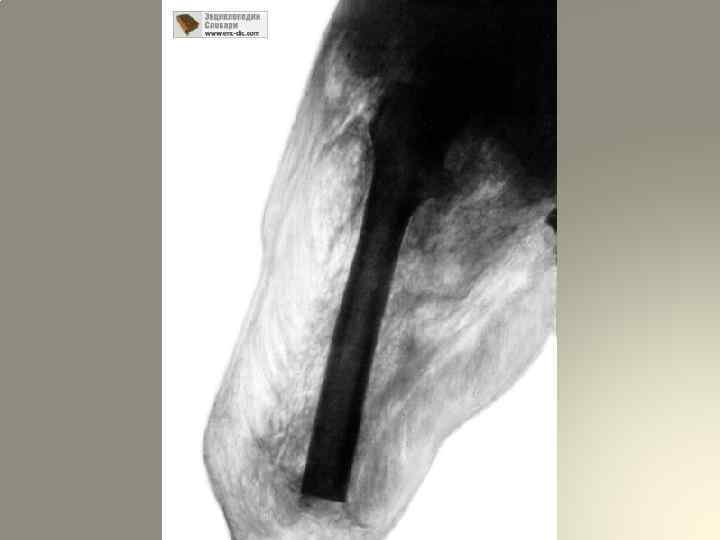

4. Газ в мягких тканях поражѐнного сегмента – достоверный симптом развития анаэробной инфекции. Газообразование, как правило, возникает вслед за развитием отѐка и свидетельствует о тканевой деструкции в результате жизнедеятельности анаэробных микроорганизмов, в первую очередь Cl. perfringens. Наличие газа определяется перкуторно: в области распространения газа выявляется тимпанический звук. В подкожной клетчатке присутствие газа можно установить путѐм пальпации – по «хрусту сухого снега» (симптом крепитации пузырьков газа). При бритье волос на коже, окружающей рану, ощущается лѐгкий треск – резонанс над пропитанным газом участком тканей ( «симптом бритвы» ). Поколачивание браншами пинцета даѐт характерный коробочный звук. Французский хирург Леметр рекомендует с диагностической целью пощѐлкивание окружности раны – получается характерный резонирующий звук

5. Отсутствие чувствительности и двигательной функции в дистальных отделах конечности – ранний и грозный симптом развития анаэробной инфекции. Эти нарушения появляются даже при внешне малых изменениях со стороны раны и конечности, являются очень важными: они помогают выявить анаэробную инфекцию, когда, на первый взгляд, других симптомов ещѐ нет. Поэтому врачам приѐмно-сортировочных отделений следует всегда иметь иглу для определения чувствительности дистальных отделов конечностей и пальцев. 6. Рентгенологическое исследование – вспомогательный метод определения газа в тканях. При распространении газа по мышечной ткани на рентгенограмме отмечаются «перистые облака» или «ѐлочки» , а при наличии газа в подкожной клетчатке изображение напоминает «пчелиные соты»